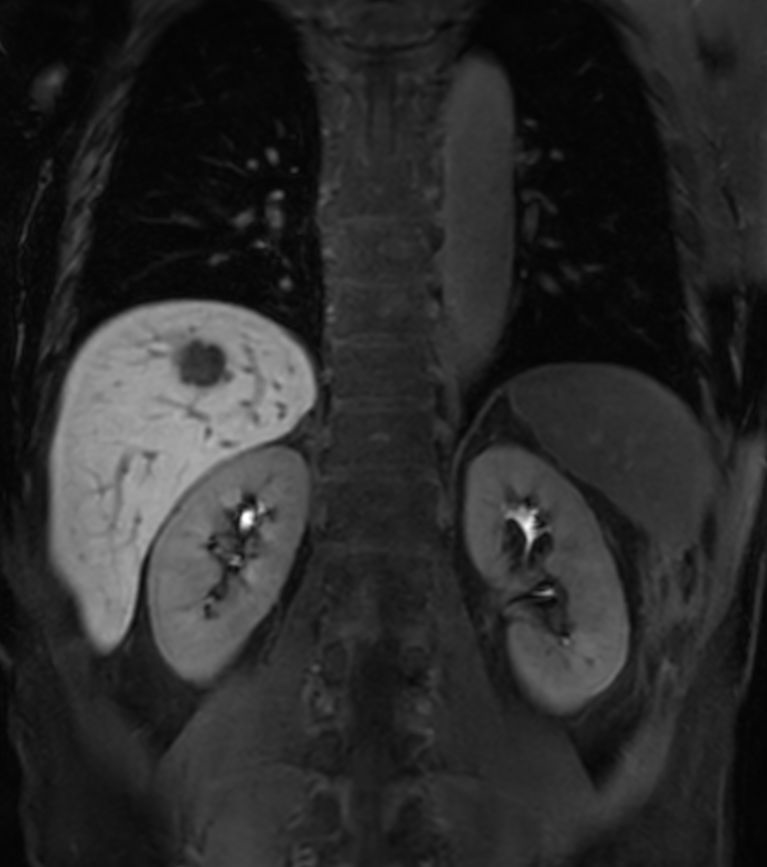

Liver metastasis – Free breathing

Patient with liver metastasis. ExamCard includes Compressed SENSE to shorten the breath hold time, VitalEye for touchless respiratory sensing, mDIXON Quant for non-invasive liver fat fraction quantification and 4D FreeBreathing to perform multi-phase contrast-enhanced MRI studies.

T1w FFE mDIXON XD - Breath hold Compressed SENSE